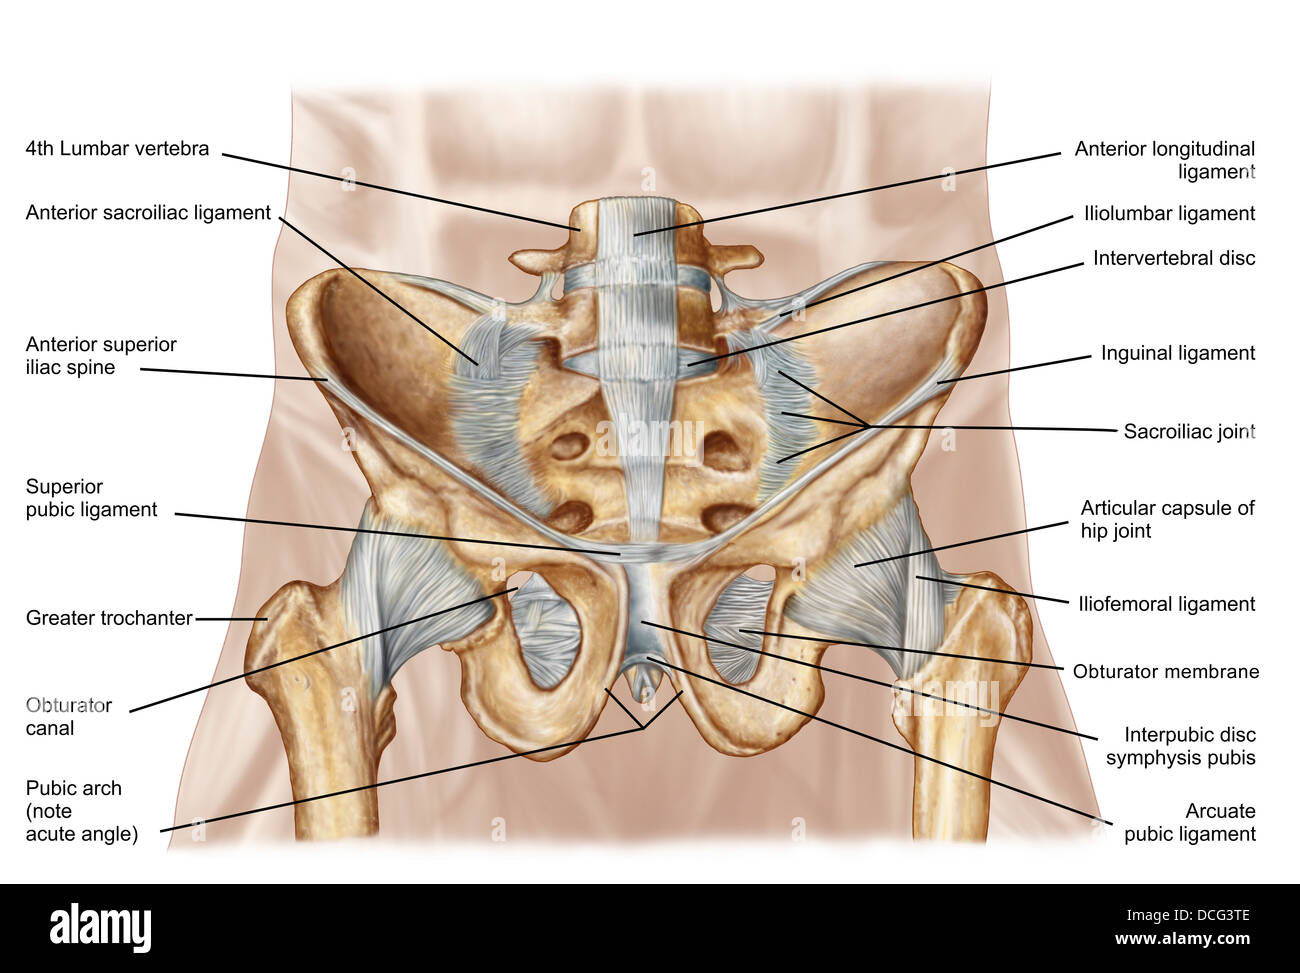

Anatomy of human pelvic bone and ligaments. Stock Photohttps://www.alamy.com/image-license-details/?v=1https://www.alamy.com/stock-photo-anatomy-of-human-pelvic-bone-and-ligaments-59361245.html

Anatomy of human pelvic bone and ligaments. Stock Photohttps://www.alamy.com/image-license-details/?v=1https://www.alamy.com/stock-photo-anatomy-of-human-pelvic-bone-and-ligaments-59361245.htmlRFDCG3TD–Anatomy of human pelvic bone and ligaments.

Anatomy of human pelvic bone and ligaments. Stock Photohttps://www.alamy.com/image-license-details/?v=1https://www.alamy.com/stock-photo-anatomy-of-human-pelvic-bone-and-ligaments-59361246.html

Anatomy of human pelvic bone and ligaments. Stock Photohttps://www.alamy.com/image-license-details/?v=1https://www.alamy.com/stock-photo-anatomy-of-human-pelvic-bone-and-ligaments-59361246.htmlRFDCG3TE–Anatomy of human pelvic bone and ligaments.